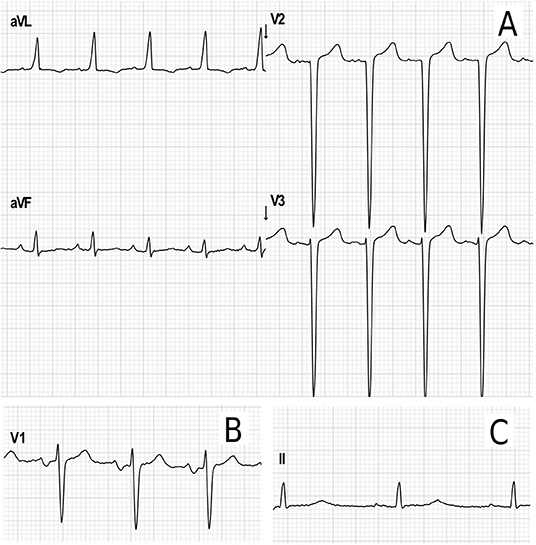

Electrocardiogram

Electrocardiograms were performed in 65 patients (45 children and 20 adults) at some point during follow-up. All patients had a sinus rhythm, although transient junctional rhythm was observed for one female with MPS IVA in the middle childhood. The most frequently observed finding was the presence of repolarization anomalies (29%) (Table 5; Figure 4A). Left ventricular hypertrophy (LVH) and left atrium enlargement were present in 5 and 8% of the patients, respectively. Atrioventricular block and long QT intervals were also occasionally observed (Figure 4C), as well as intraventricular blocks. As compared to children, adults had a higher prevalence of most of the ECG abnormalities (Table 6), particularly ventricular repolarization abnormalities (Figure 4A) and left atrial enlargement (Figure 4B).

Figure 4. Representative electrocardiographic abnormalities identified in the adult patients of this study. (A) Electrocardiographic criteria for left ventricular hypertrophy (Cornell index: 40 mm) and repolarization abnormalities in a female in the age range of 26–30 years with MPS IVA. (B) Left atrium enlargement in a male in the age range of 21–25 years with MPS II (terminal negative deflection within the P wave in lead V1). (C) Increased PR interval (203 ms) and transient prolonged QTc (464 ms) in female in the age range of 31–35 years with MPS I during postoperative care for aortic valve and mitral valve replacement.